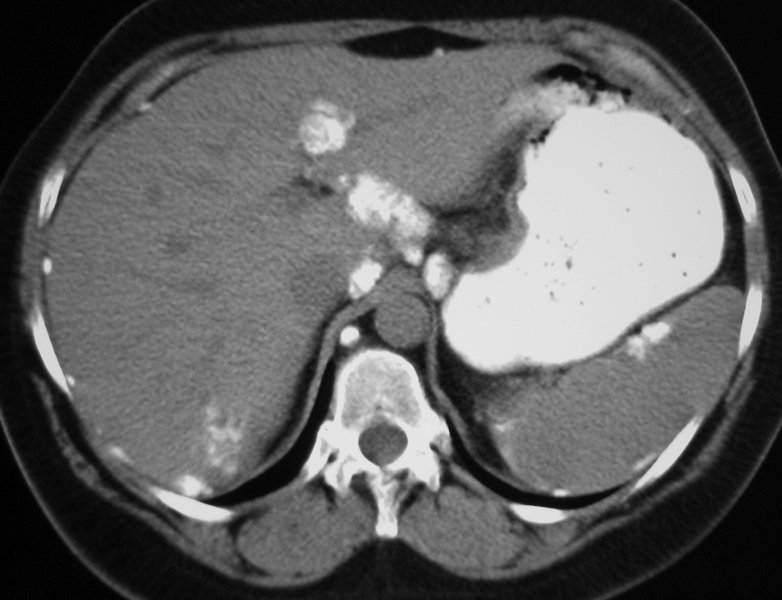

What do you see? What does this MOST likely suggest?

Multiple amorphous calcifications within the liver and studding the peritoneal surface of the abdomen. This pt had a mucin-producing adenoCA of the ovary that metastasized to the peritoneum and liver. While mucin-producing tumors of the stomach and colin can also produced calcified mets, ovarian malignancy would be the most common to metastasize to the peritoneum.